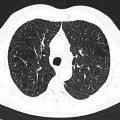

Coronavirus – COVID 19

• Opacités en verre dépoli (présentes chez tous les patients hospitalisés)

• Multiples

• Triangulaires

• Périphériques

• Bilatérales

• A prédominance basale

• Aspect de crazy paving

• Verre dépoli

• Épaississements inter et intra lobulaires

• Condensations alvéolaires

• Élargissements vasculaires au sein des lésions

• Bronchectasies par traction